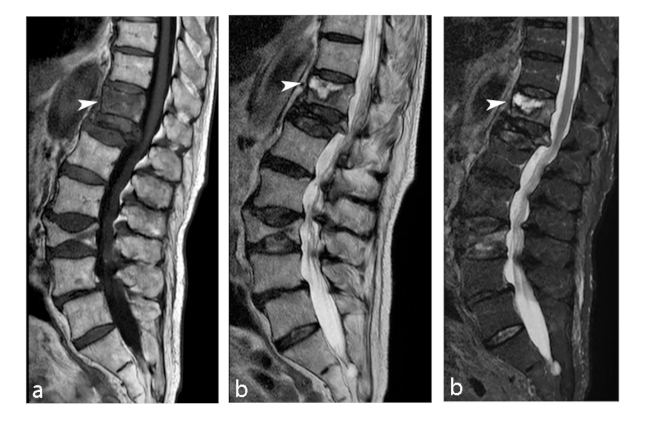

La ON vertebral es una patología poco frecuente. Se postula que la fisiopatología es la consecuencia de la afección del segmento anterior del cuerpo vertebral, por mecanismos traumáticos o no traumáticos.12 En el primer caso, se lo llama enfermedad de Kummel y representa un colapso vertebral tardío después de un traumatismo, el cual inicialmente es asintomático acompañado de una radiografías (RX) poco notable que gradualmente se vuelve sintomática y resulta en colapso del cuerpo vertebral.13 El segundo mecanismo implica fracturas microtrabeculares repetidas en un cuerpo vertebral que se debilita, y se encuentra asociado al abuso de alcohol, infecciones, glucocorticoides, dislipidemia, enfermedad de Gaucher, inmunodeficiencias, entre otras causas.12

Los hallazgos por imágenes de la ON vertebral se pueden acompañar de una colección de aire intravertebral, observándose el signo de la hendidura en descripción a un área radiolúcida semilunar o lineal en las RX o en tomografía computada (TC). Generalmente se encuentra en el área central o adyacente al platillo terminal.14

En RM, además de los hallazgos característicos de la ON per se (►Fig. 7), se puede evidenciar una intensidad de señal baja en todas las secuencias y aparece como un vacío de señal en las imágenes de eco de gradiente, debido al efecto de susceptibilidad magnética del aire. También se puede observar una colección líquida en el cuerpo vertebral, que se visualiza como un área circunscripta hipointensa ponderada en T1 e hiperintensa ponderada en T2.15